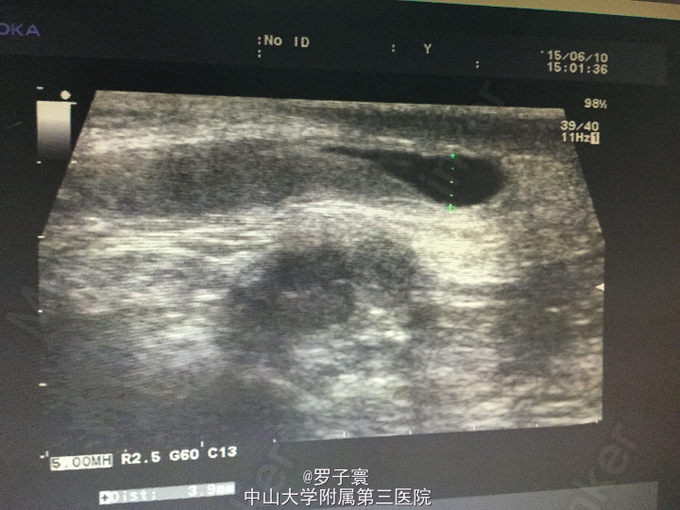

查体:阴茎呈男童外观,包茎,左侧阴囊空虚,未触及任何内容物,左侧腹股沟可触及睾丸样团块,质地软,大小1.4*0.6cm,无触痛,无粘连,站立活动后右侧阴囊可触及质软肿物,透过试验阳性,可扪及右侧睾丸,大小约1.5*0.8cm,触诊质地软,表面光滑,无硬结,无压痛,附睾、精索触诊不满意。生殖系彩超(我院,2015-06-10):双侧阴囊内睾丸缺如;双侧腹股沟部隐睾(左侧活动度大);右侧睾丸鞘膜积液。